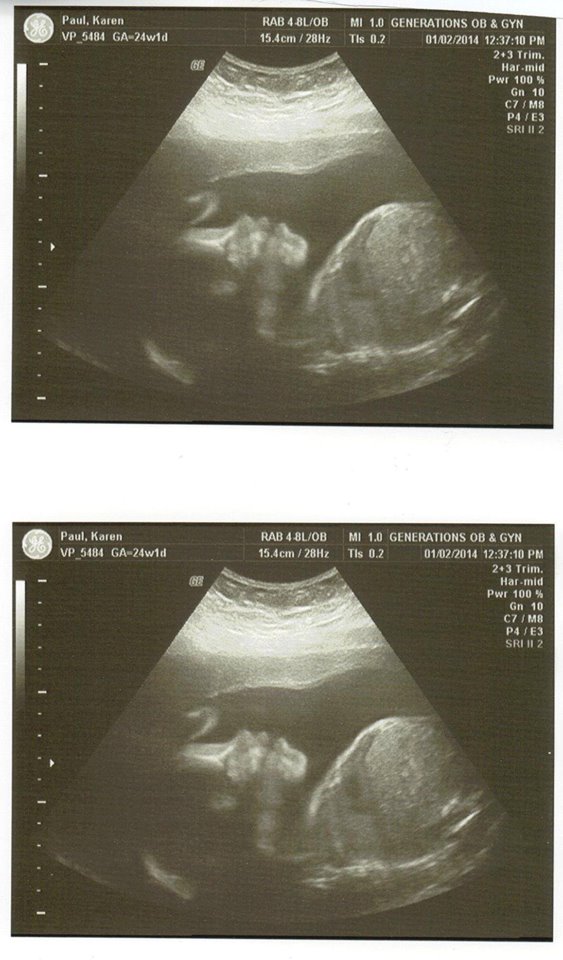

Pregnancy

Pregnancy Photos